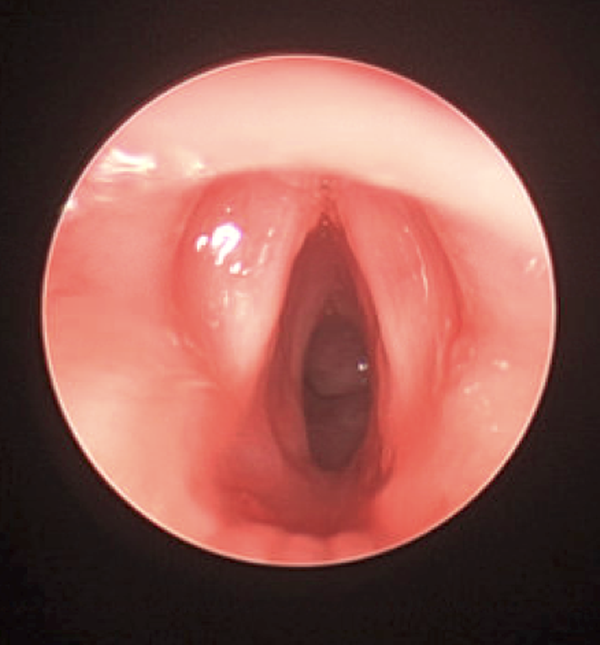

Subglottic Stenosis